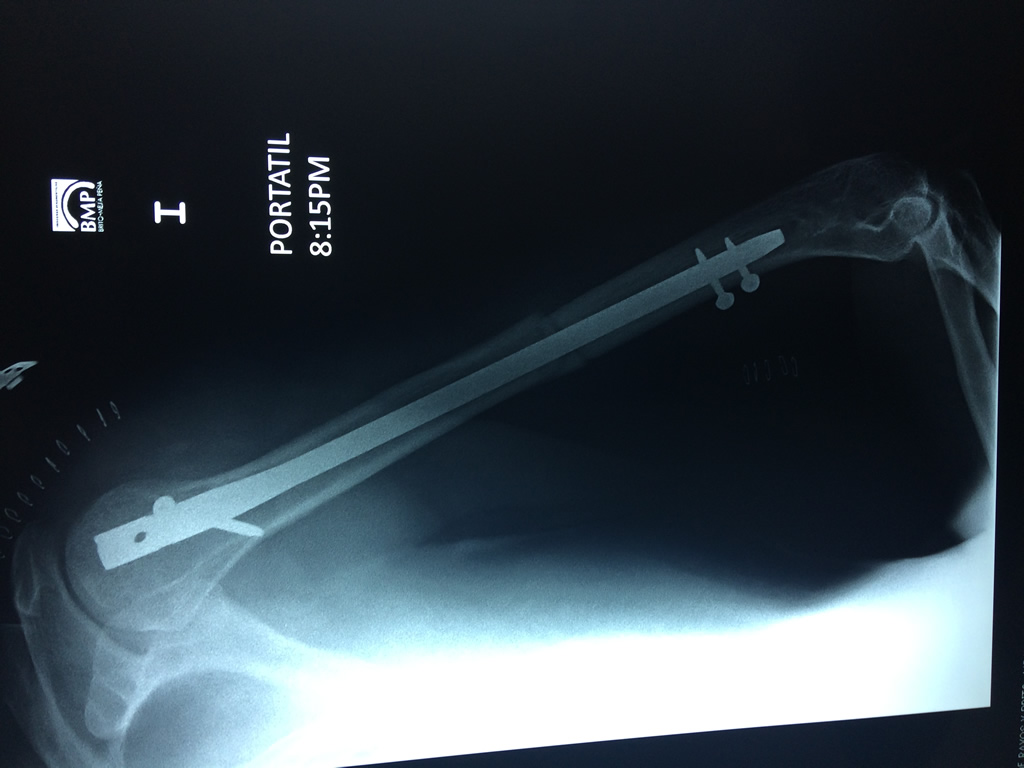

Fémur - Húmero

El Húmero (en latín, humerus) es el hueso más largo de las extremidades superiores en el ser humano. Forma parte del esqueleto apendicular superior y está ubicado en la región del brazo. ... El extremo proximal del húmero tiene la cabeza, cuellos quirúrgico y anatómico y tubérculos mayor y menor.